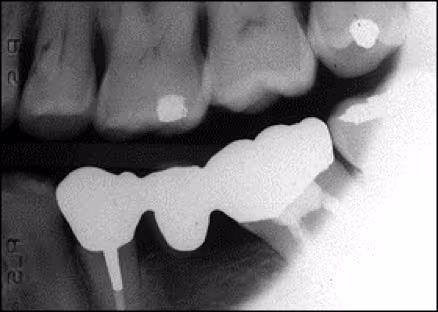

Figure 12: Bitewing – Mandibular Bone Margin Cut Off

Missing apices can be caused by a receptor placement error (Figure 11). When using receptor holders, the bite block should be placed on the incisal or occlusal aspect of the teeth to be imaged and not on the opposing teeth. If the bite block is placed on the opposing teeth and the patient is required to bite the receptor into place, a placement error is likely to occur. Placing the receptor more lingual to the teeth where the palate and floor are deeper will make positioning easier and more comfortable for the patient. This is important when placing the receptor for bitewings so that the receptor is not displaced by anatomical structures (Figure 12). Placement of the bite block and receptor in the correct position first and then having the patient slowly bite to maintain the placement is the preferred and most effective approach.